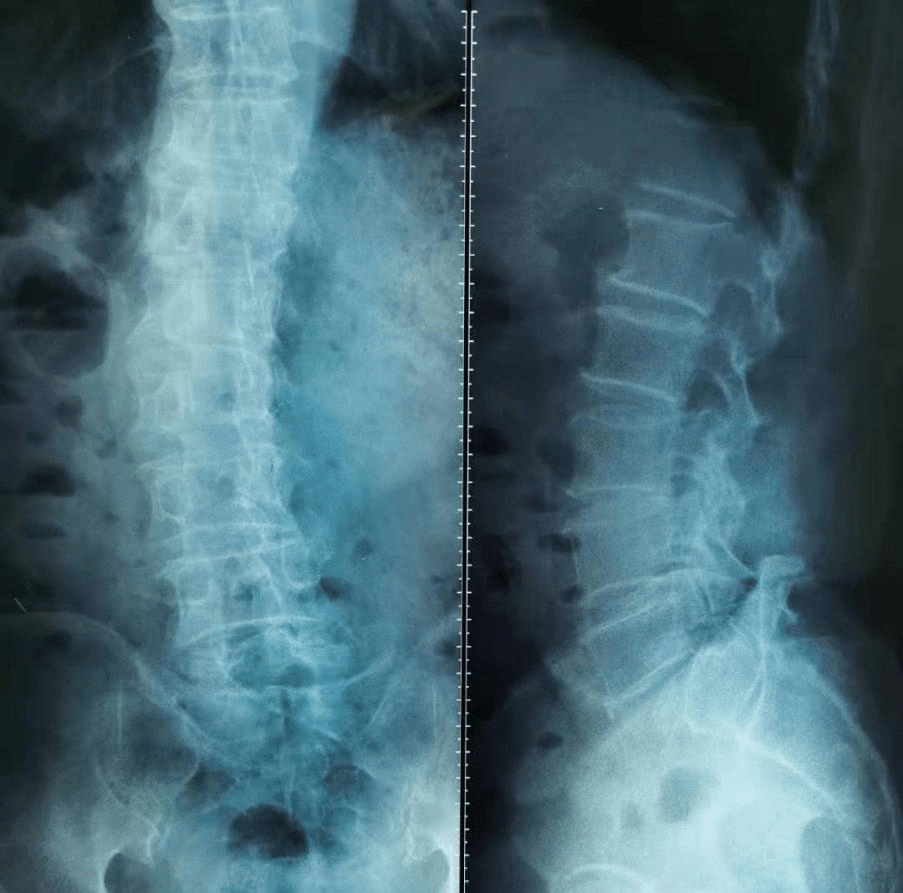

像老李这样“五十岁的人 , 八十岁的腰”的情况并不少见 , 医学上统称为“腰椎退行性病变” , 就是腰椎间盘与关节突出关节的关节软骨与周围韧带发生了生理性的退行性病变 , 从而导致腰腿痛一类疾病的总称 , 主要包括退变性腰椎滑脱症与椎管狭窄、退变性腰椎侧弯与退变性椎间盘突出等 。 研究报道70-90%人群一生中出现过腰疼症状 , 其中相当大一部分与腰椎退变相关 。

退变性腰椎不稳的发展往往有三个阶段:功能障碍阶段、腰椎失稳阶段、再稳定阶段 。 在早期的功能障碍阶段 , 躯干肌退变及椎间盘退变是主要的诱发因素 , 比如随着年龄的增长 , 躯干肌中脂肪渗入会逐渐增多 , 臀大肌、腹横肌、椎旁肌及腰大肌脂肪浸润都与椎间盘退变相关 。 这个阶段得不到纠正的话 , 就会进入到下一步腰椎失稳阶段 , 此时由于躯干肌及椎间盘退变 , 导致腰椎相关韧带及关节囊松弛 , 小关节应力增加并诱发关节炎症出现 , 使得腰椎节段稳定性减退并出现不稳定的情况——这个阶段腰痛、坐骨神经痛等症状会明显加重 , 严重影响病人生活质量和工作效率 。